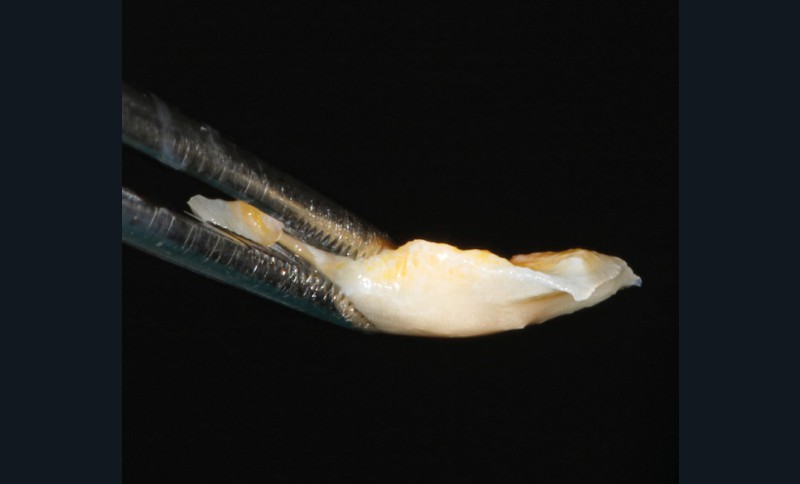

- Parmi ces longueurs d’onde, deux lasers (Er-YAG et Diode) sont intéressants dans le traitement de la péri-implantite :

– Le laser Er-YAG, utilisé pour le nettoyage, est un laser avec un milieu actif composé d’yttrium, d’aluminium et de grenat dopé à l’erbium. Avec une longueur d’onde de 2 940 nm situé dans l’infrarouge, le laser Er-YAG est un laser à haute énergie, dont la lumière est absorbée dans l’eau et dans l’hydroxyapatite et qui ne pénètre pas profondément. Ceci permet de couper des tissus mous et des tissus durs, mais également de désorganiser le biofilm bactérie.